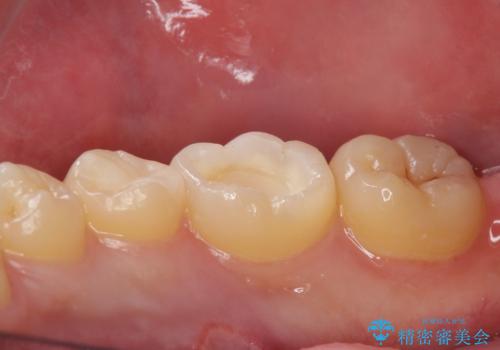

古い樹脂を除去してe-maxインレー

拡大鏡下で古い樹脂を除去し、虫歯がない事を確認してe-maxインレーで治療を行いました。

適合の良い詰め物が入りました。

セラミックは虫歯の再発のリスクが少ないです。